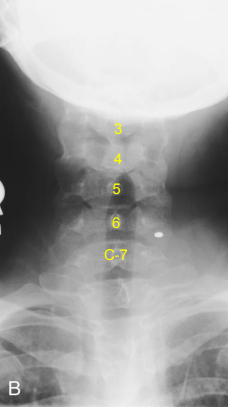

AP Axial C-Spine: Eval Criteria

Angle CR 15 to 20 degree cephalad neck extended slightly

C3 to T2 demoed

Space between pedicles and intervertebral disk spaces clearly seen

Mandible and base of the skull should superimpose C1-2

AP Axial C-Spine: Is this Image Good?

No.

Vertebral body of C3 is partially superimposed by base of skull

Incorrect CR angle (caudal) produced foreshortening of vertebral bodies and closure of intervertebral joint spaces

Excessive extension superimposed base of skull over upper C-Spine

Correct the angle and adjust head so that a line from lower margin of upper incisors to the base of the skull is perp. to IR